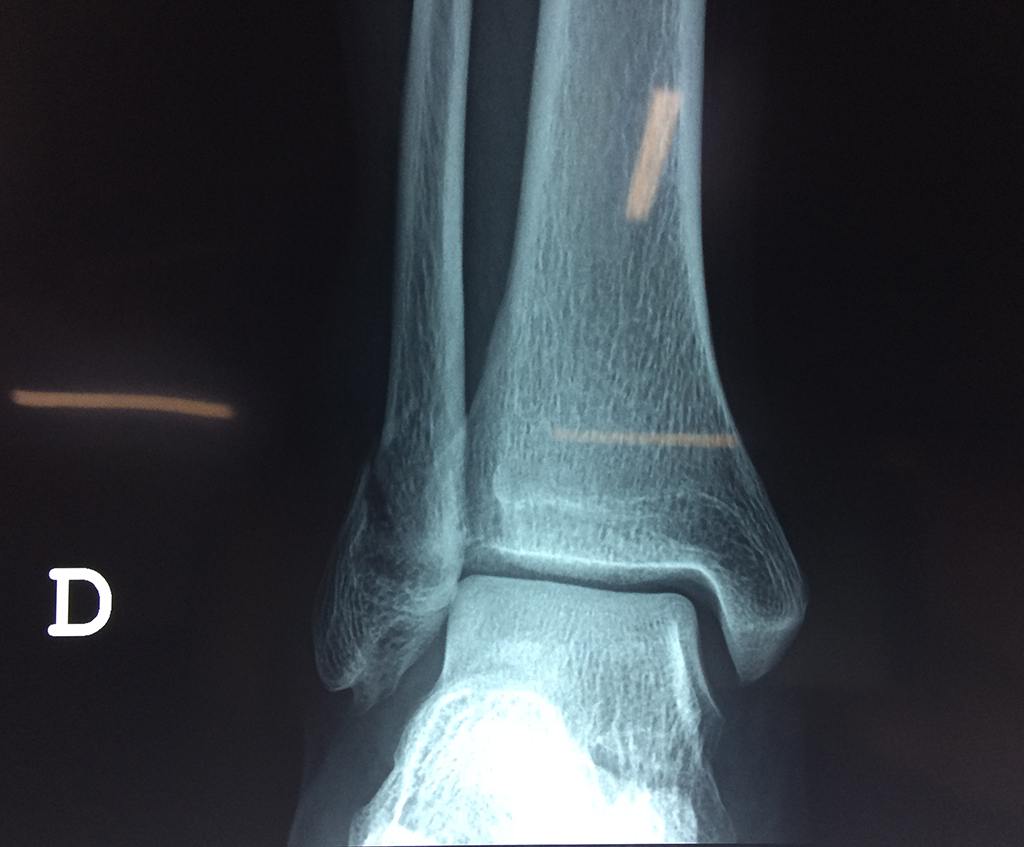

Una fractura de tobillo es la rotura de uno o más de los huesos del tobillo. Estas fracturas pueden ser:

- Parciales (el hueso está sólo parcialmente fisurado, no del todo).

- Completas (el hueso está perforado y está en 2 partes).

- Producirse en uno o ambos lados del tobillo.

Algunas fracturas de tobillo pueden requerir cirugía si:

- Los extremos de los huesos están desalineados entre sí (desplazados).

- La fractura se extiende hasta la articulación del tobillo (fractura intra-articular).

- Los tendones o ligamentos (tejidos que sujetan los músculos y los huesos entre sí) están rotos.

- El médico cree que sus huesos probablemente no sanen apropiadamente sin cirugía.

- El médico considera que la cirugía puede permitirle una recuperación más rápida y confiable.

- En los niños, la fractura involucra la parte del hueso del tobillo donde el hueso está creciendo.